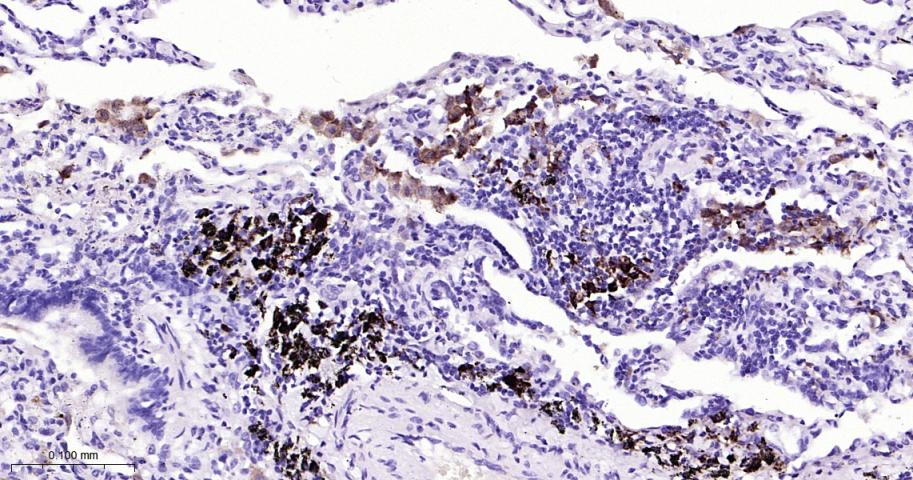

Paraformaldehyde-fixed, paraffin embedded Human Lung; Antigen retrieval by boiling in sodium citrate buffer (pH6.0) for 15 min; The section was incubated with TRAP  Monoclonal Antibody, Unconjugated (bsm-61758R) at 1:200 overnight at 4°C, followed by conjugation to the bs-0295G-HRP and DAB (C-0010) staining.